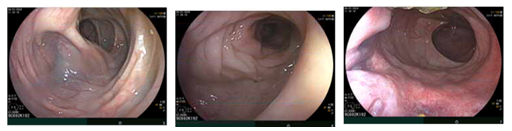

Nội soi đại trực tràng:

Hình 7: Hình ảnh nội soi đại trực tràng bình thường. Trĩ nội độ I.

Từ kết quả mô bệnh học và hóa mô miễn dịch trên nghĩ nhiều đến ung thư đường tiêu hóa dưới (đại, trực tràng). Tuy nhiên kết quả nội soi đại trực tràng lần 1 không phát hiện tổn thương. Dữ liệu ủng hộ nhiều về ung thư tiêu hóa do đó bệnh nhân được chỉ định nội soi lại đại trực tràng lần 2 và có đề nghị bác sĩ nội soi kiểm tra cẩn thận trong lần này.

Nội soi đại trực tràng lần 2:

Hình 8: Trực tràng cách rìa hậu môn ~12cm có tổn thương thâm nhiễm co kéo niêm mạc xung quanh (mũi tên vàng), sinh thiết tổn thương làm mô bệnh học.